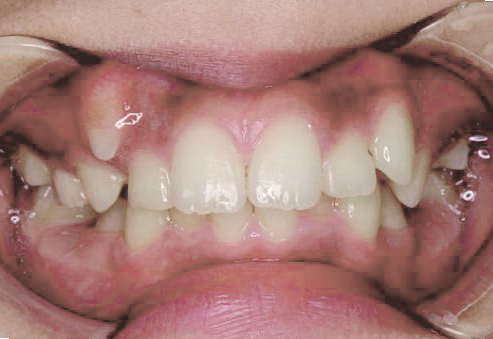

八重歯になっちゃった…歯が入る隙間がないけど、永久歯は抜きたくない!

Aさん (矯正開始時:9歳)

Before

After

すっきりしたお顔立ちの女の子ですが、外側から八重歯が生えてきてしまいました。

治療を終えて

マイオブレイスとBWS装置を使い、あごの骨や歯並びの形を整えながら、鼻呼吸や正しい飲み込み方も身に付けることができました。

お口の悪いクセは改善され、お子さん自身の力でしっかりとしたかみ合わせができるようになりました。ご希望通り永久歯を抜く必要はありませんでした。

主訴・治療内容 他院で「永久歯を抜いて矯正」をすすめられたが抜歯に抵抗があり「永久歯を抜かずに、あごの骨から整えてくれる」と口コミを見て当院を選んでくださいました。

治療期間 2年

費用 495,000円(税込)